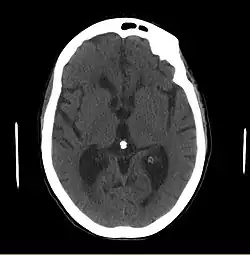

Le diagnostic de l'HPN est généralement orienté par une imagerie cérébrale pour éliminer tout processus lésionnel . une ponction lombaire sera demandé par la suite, avec possible drainage externe quotidien du liquide cérébrospinal pour trois à quatre jours avec évaluation de la réponse clinique.

- Le scanner cérébral peut montrer une dilatation ventriculaire disproportionnée par rapport à l’atrophie corticale avec élargissement des cornes frontales et arrondissement des cornes temporales sans atrophie de l'hippocampe.

- L'IRM cérébrale, en plus de la dilatation, permet de mettre en évidence d'autres affections du système nerveux central, soit des diagnostics différentiels ou bien des facteurs affectant le pronostic du patient.